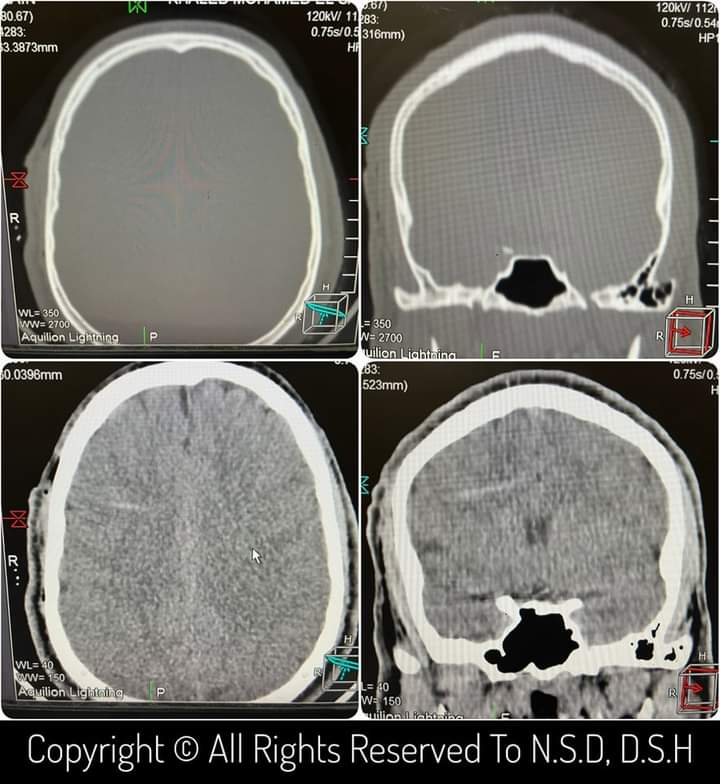

وبعد عمل أشعة مقطعية على المخ تبين وجود جسم غريب (مسمار) مخترق لعظام الجمجمة ونصف حجم المخ في إصابة مباشرة لشريان من شرايين المخ.

وتم على الفور عمل أشعة مقطعية علي المخ بعد انتهاء الجراحه مباشرة وتحت تأثير التخدير الكلي ليتبين عدم وجود نزيف .

وتم خروج المريض بدرجة وعي كاملة مع كامل القوة الحركية، وتم إعادة الأشعة المقطعية على المخ مرة اخري بعد 24 ساعة للتأكد من عدم وجود أي نزيف.